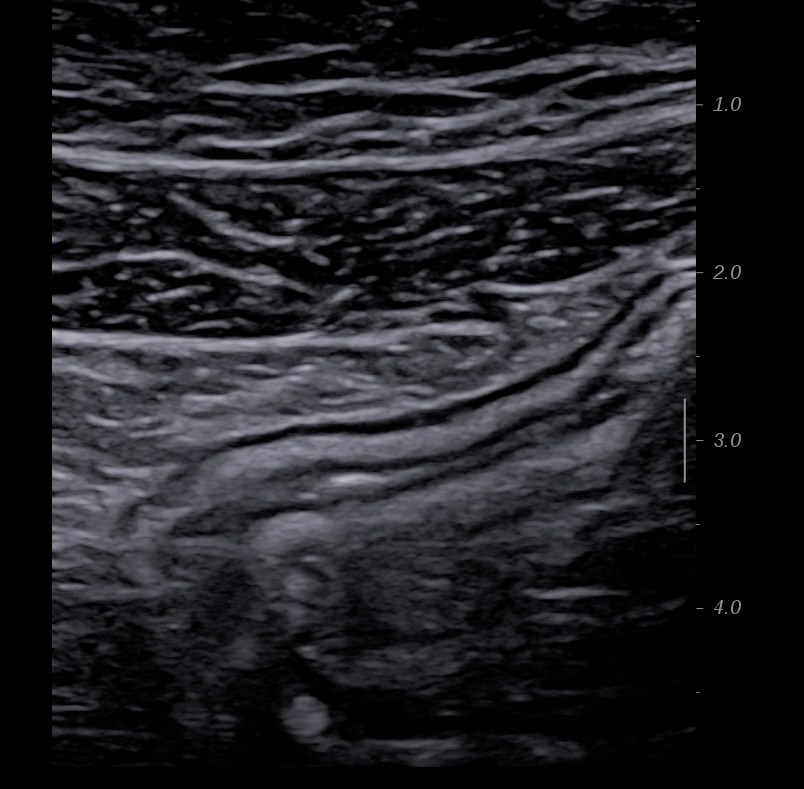

En basse fréquence la musculeuse épaissie hypoéchogène souligne les parois du sigmoide

Epaississement musculeuse et image diverticulaire

Musculeuse sigmoidienne épaissie paroi non inflammée